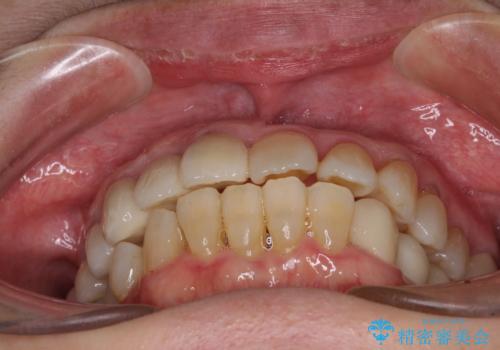

数多くの外科処置を行ったため、治療期間は長期間となりました。

一方、外科処置をしっかりと行ったことで、歯周病の状態は改善され、安定した状態にしあげることができました。